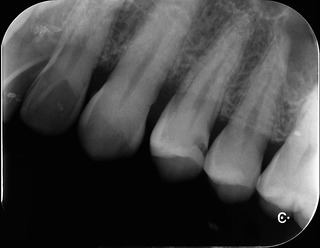

レントゲン

歯と歯の間に黒い病変が‥